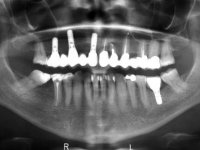

•    Metal-ceramic fixed partial denture (FPD) (11-15) supported by three dental implants in 11, 13 and 15.

•    Metal-ceramic FPD over teeth 21-22-23-25.

•    Small exposure of the implant neck in 11 position.

•    Significant root exposure on teeth 21 and 22.

•    In the lower jaw, patient had edentulous spaces in 46 and 36, and tooth 47 is tilted mesially.